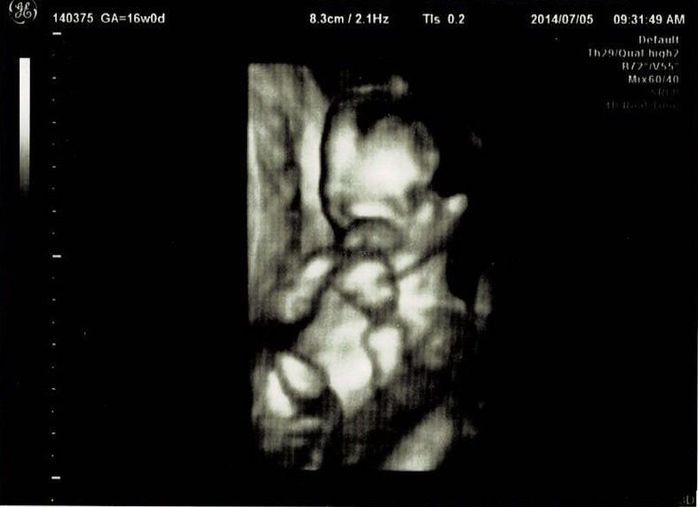

妊娠16週目エコー写真

初めての3Dエコーでした。今までレントゲンのようなエコー写真でしか赤ちゃんを見ていなかったので、芋虫みたいな見た目でも、「ちゃんと人間だ!」と不思議な気持ちになりました。エコーを見るたびに、「本当に人間ができているんだなぁ」と、毎回特別な気持ちになります。3Dエコーは、なんとなくこちらを見ている感じがして、かわいらしいと思ったり。手を口元に寄せて、すでに赤ちゃんらしい丸っこいポーズをしています。

この日は、BPD(頭の左右幅)、AC(おなかの周りの長さ)、FL(太ももの骨の長さ)を測って、赤ちゃんの育ちぐあいを見てくれました。このエコーは足の骨を測っているところです。足の指らしき骨も見えます。先生がスムーズに赤ちゃんの頭やおなか、足を探すのが面白く、測っている最中のエコーもずっと眺めていました。